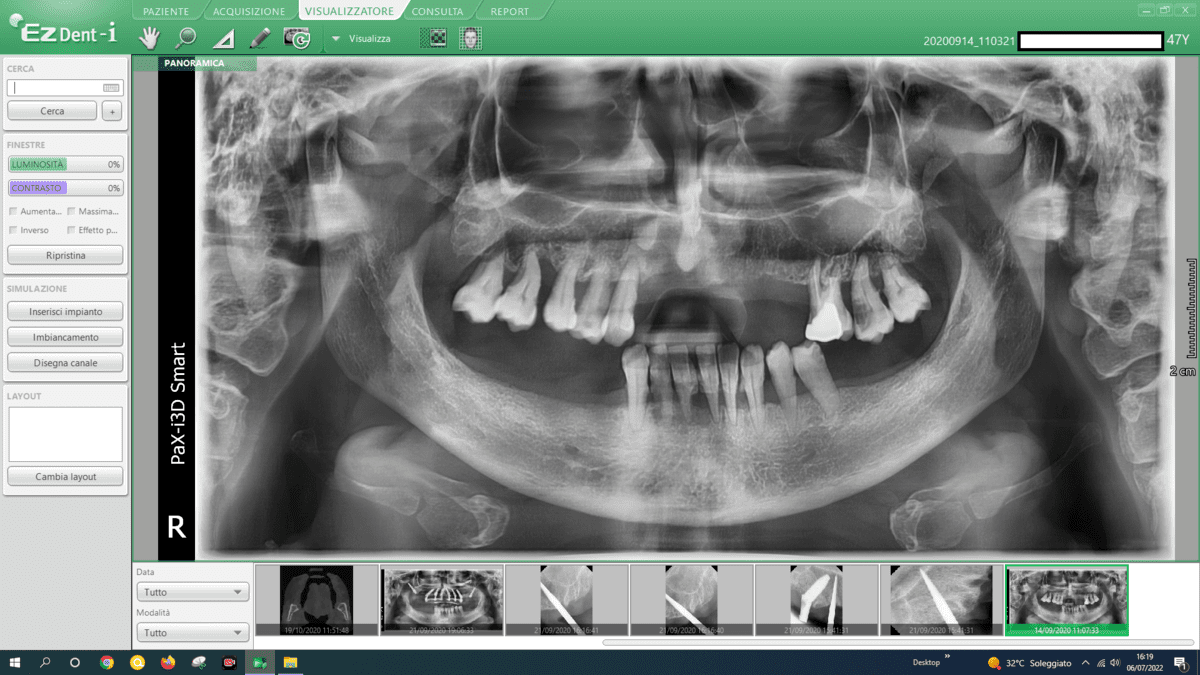

In addressing mandibular atrophies, our approach revolves around utilizing advanced implant techniques that offer superior outcomes compared to traditional methods like autologous bone grafts. Here’s a breakdown of our considerations:

- Transverse Implants:

- We employ transverse implants, strategically placed across the mandible. This technique provides stability and support, avoiding the need for extensive bone grafting.

- Blade Implants:

- Blade implants are another key component of our approach. These implants are designed for efficient insertion, providing secure anchorage in atrophic areas without the challenges associated with autologous bone grafts.

- Grid-Like Subperiosteal Implants:

- Our practice utilizes subperiosteal implants configured in a grid-like pattern. This innovative approach optimizes bone contact, ensuring a strong foundation for the implants. This technique eliminates the necessity for autologous bone grafts and their associated complexities.

- Split Crest Procedures:

- Split crest procedures are implemented to widen the alveolar ridge, creating space for implant placement. This technique enhances bone volume and facilitates the successful integration of implants, avoiding the need for time-consuming autologous bone grafts.

- Avoidance of Autologous Bone Grafts:

- We intentionally steer clear of autologous bone grafts due to their drawbacks, including extended surgical procedures, heightened pain levels, and potential complications. Our chosen techniques are not only more efficient but also offer predictability, minimizing the risk of infections and ensuring a smoother recovery.

By embracing these advanced implant techniques, we prioritize patient comfort, reduce procedural complexities, and enhance the overall success and predictability of the treatment. Our commitment lies in providing innovative solutions that not only address mandibular atrophies effectively but also offer a more streamlined and reliable alternative to traditional approaches.